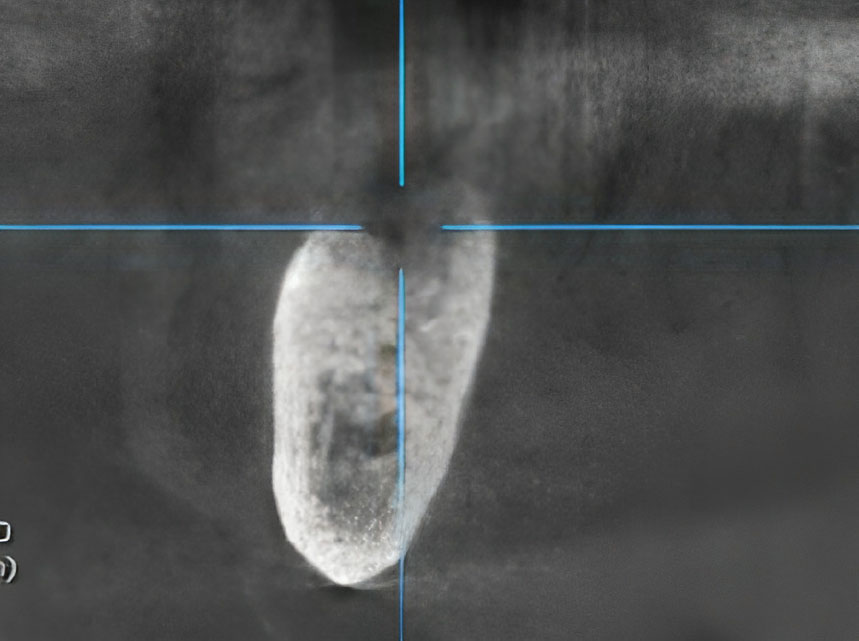

Surgical intervention was then performed under local anesthesia, consisting of sequestrectomy. The procedure involved the en bloc removal of the necrotic bone, which included the previously osseointegrated dental implant. A postoperative CBCT was obtained (Fig. 4). The surgical site was packed with iodoform gauze, which was left in place for seven days.

Axial CT projection showing the dimensions of the bone defect immediately following surgical sequestrectomy.